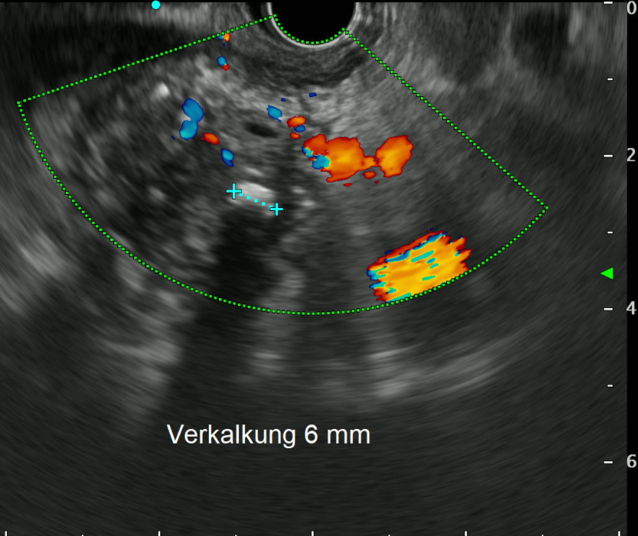

Die Diagnose der Erkrankung wird durch bildmorphologische Veränderungen, Anamnese und die klinische Symptomatik (Schmerzen/Zeichen einer Malnutrition) gestellt. Die frühe chronische Pankreatitis stellt eine Herausforderung dar. Oft kommt es im Vorfeld zu rezidivierenden akuten Exazerbationen der Erkrankung, bis nach Jahren oder erst Jahrzenten die typischen morphologischen Veränderungen fassbar werden [6]. Bei Verdacht und nicht eindeutigen Veränderungen in der Bildgebung kann, in Kombination mit dem typischen Symptomkomplex aus Oberbauchschmerz, Lipaseerhöhung, exokriner Insuffizienz (oder auch bekannte Hochrisikomutationen) die Diagnose dennoch gestellt werden [3]. Um der Diagnose nachzugehen, ist in frühen Stadien auch eine Zuweisung zur Endosonographie (EUS) sinnvoll (Abb. 1). Diese kann anhand früher Parenchym- und Gangveränderungen (Verkalkungen, Lobularität etc.) gegebenenfalls den Verdacht bestätigen. Eine klare Indikation zur Biopsie zwecks Abklärung der Ätiologie stellt derzeit nur der Verdacht auf eine AIP dar [1]. Obwohl von amerikanischen Guidelines empfohlen, sollte eine Biopsie bei Verdacht auf chronische Pankreatitis nur nach sorgfältiger Abwägung des Nutzen-Risiko-Verhältnisses vorgenommen werden – besonders mit Hintergrund der niedrigen Sensitivität dieser Untersuchung [7].

Abb. 1

Endosonographische Darstellung des Pankreas mit Zeichen der chronischen Pankreatitis